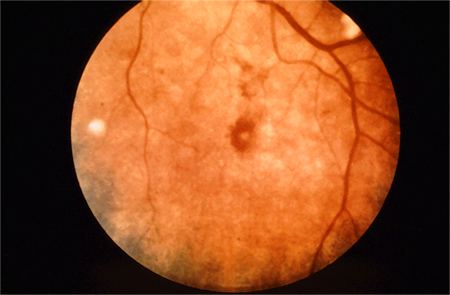

- Roth spots